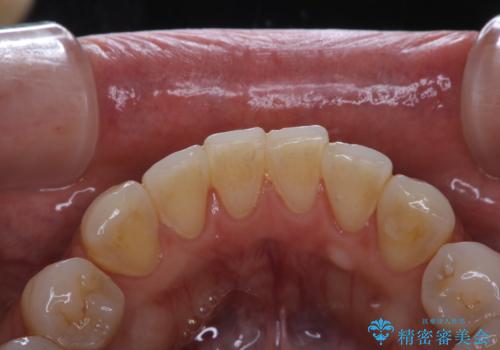

- フロスが以前よりも通りずらくなり、クリーニングしてほしいとのことでした。歯科医院でのクリーニングは3年ぶりとのことです。PMTC60分コースを行いました。

歯石が溜まると、歯と歯の間が埋め尽くされてしまい、デンタルフロスが通りずらくなったり、通せなくなります。